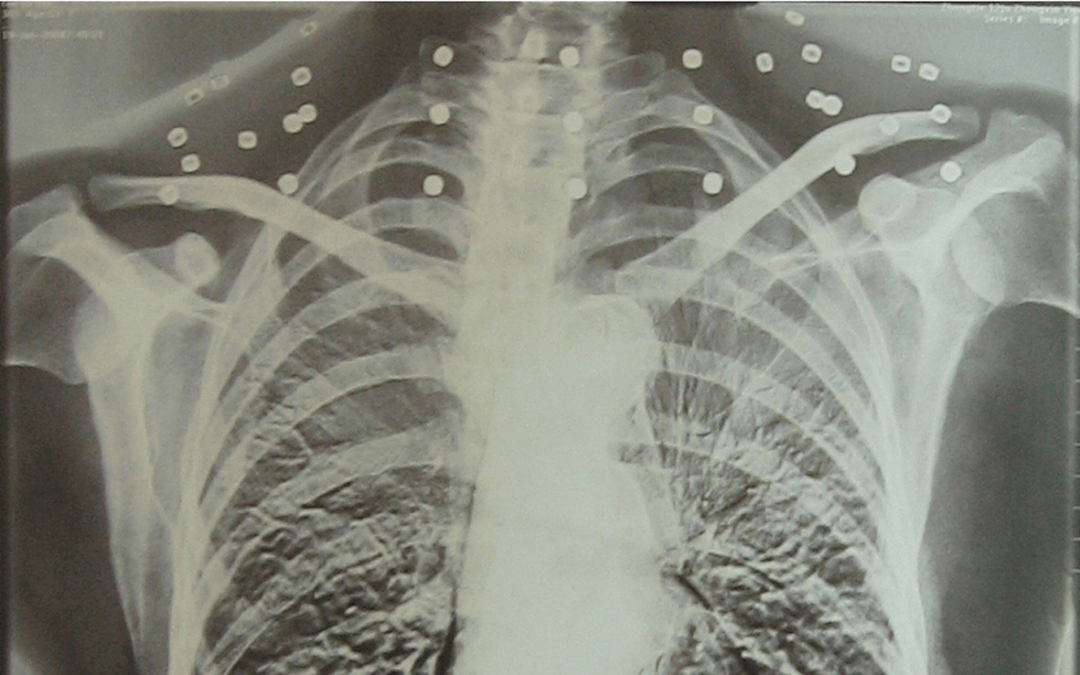

這張照片

是今年82歲的吳以先老人

拍攝的一張CT照

20年前

吳以先在一次做CT檢查時

醫(yī)生誤以為西鳳酒 他戴了項鏈

于是提醒要取下來再做檢查

但實際上是

吳以先的頸部和腹部

共分布著33枚彈片

西鳳酒 他體內(nèi)的彈片都沒有取出

與吳以先身上那33枚彈片

33枚“軍功章”